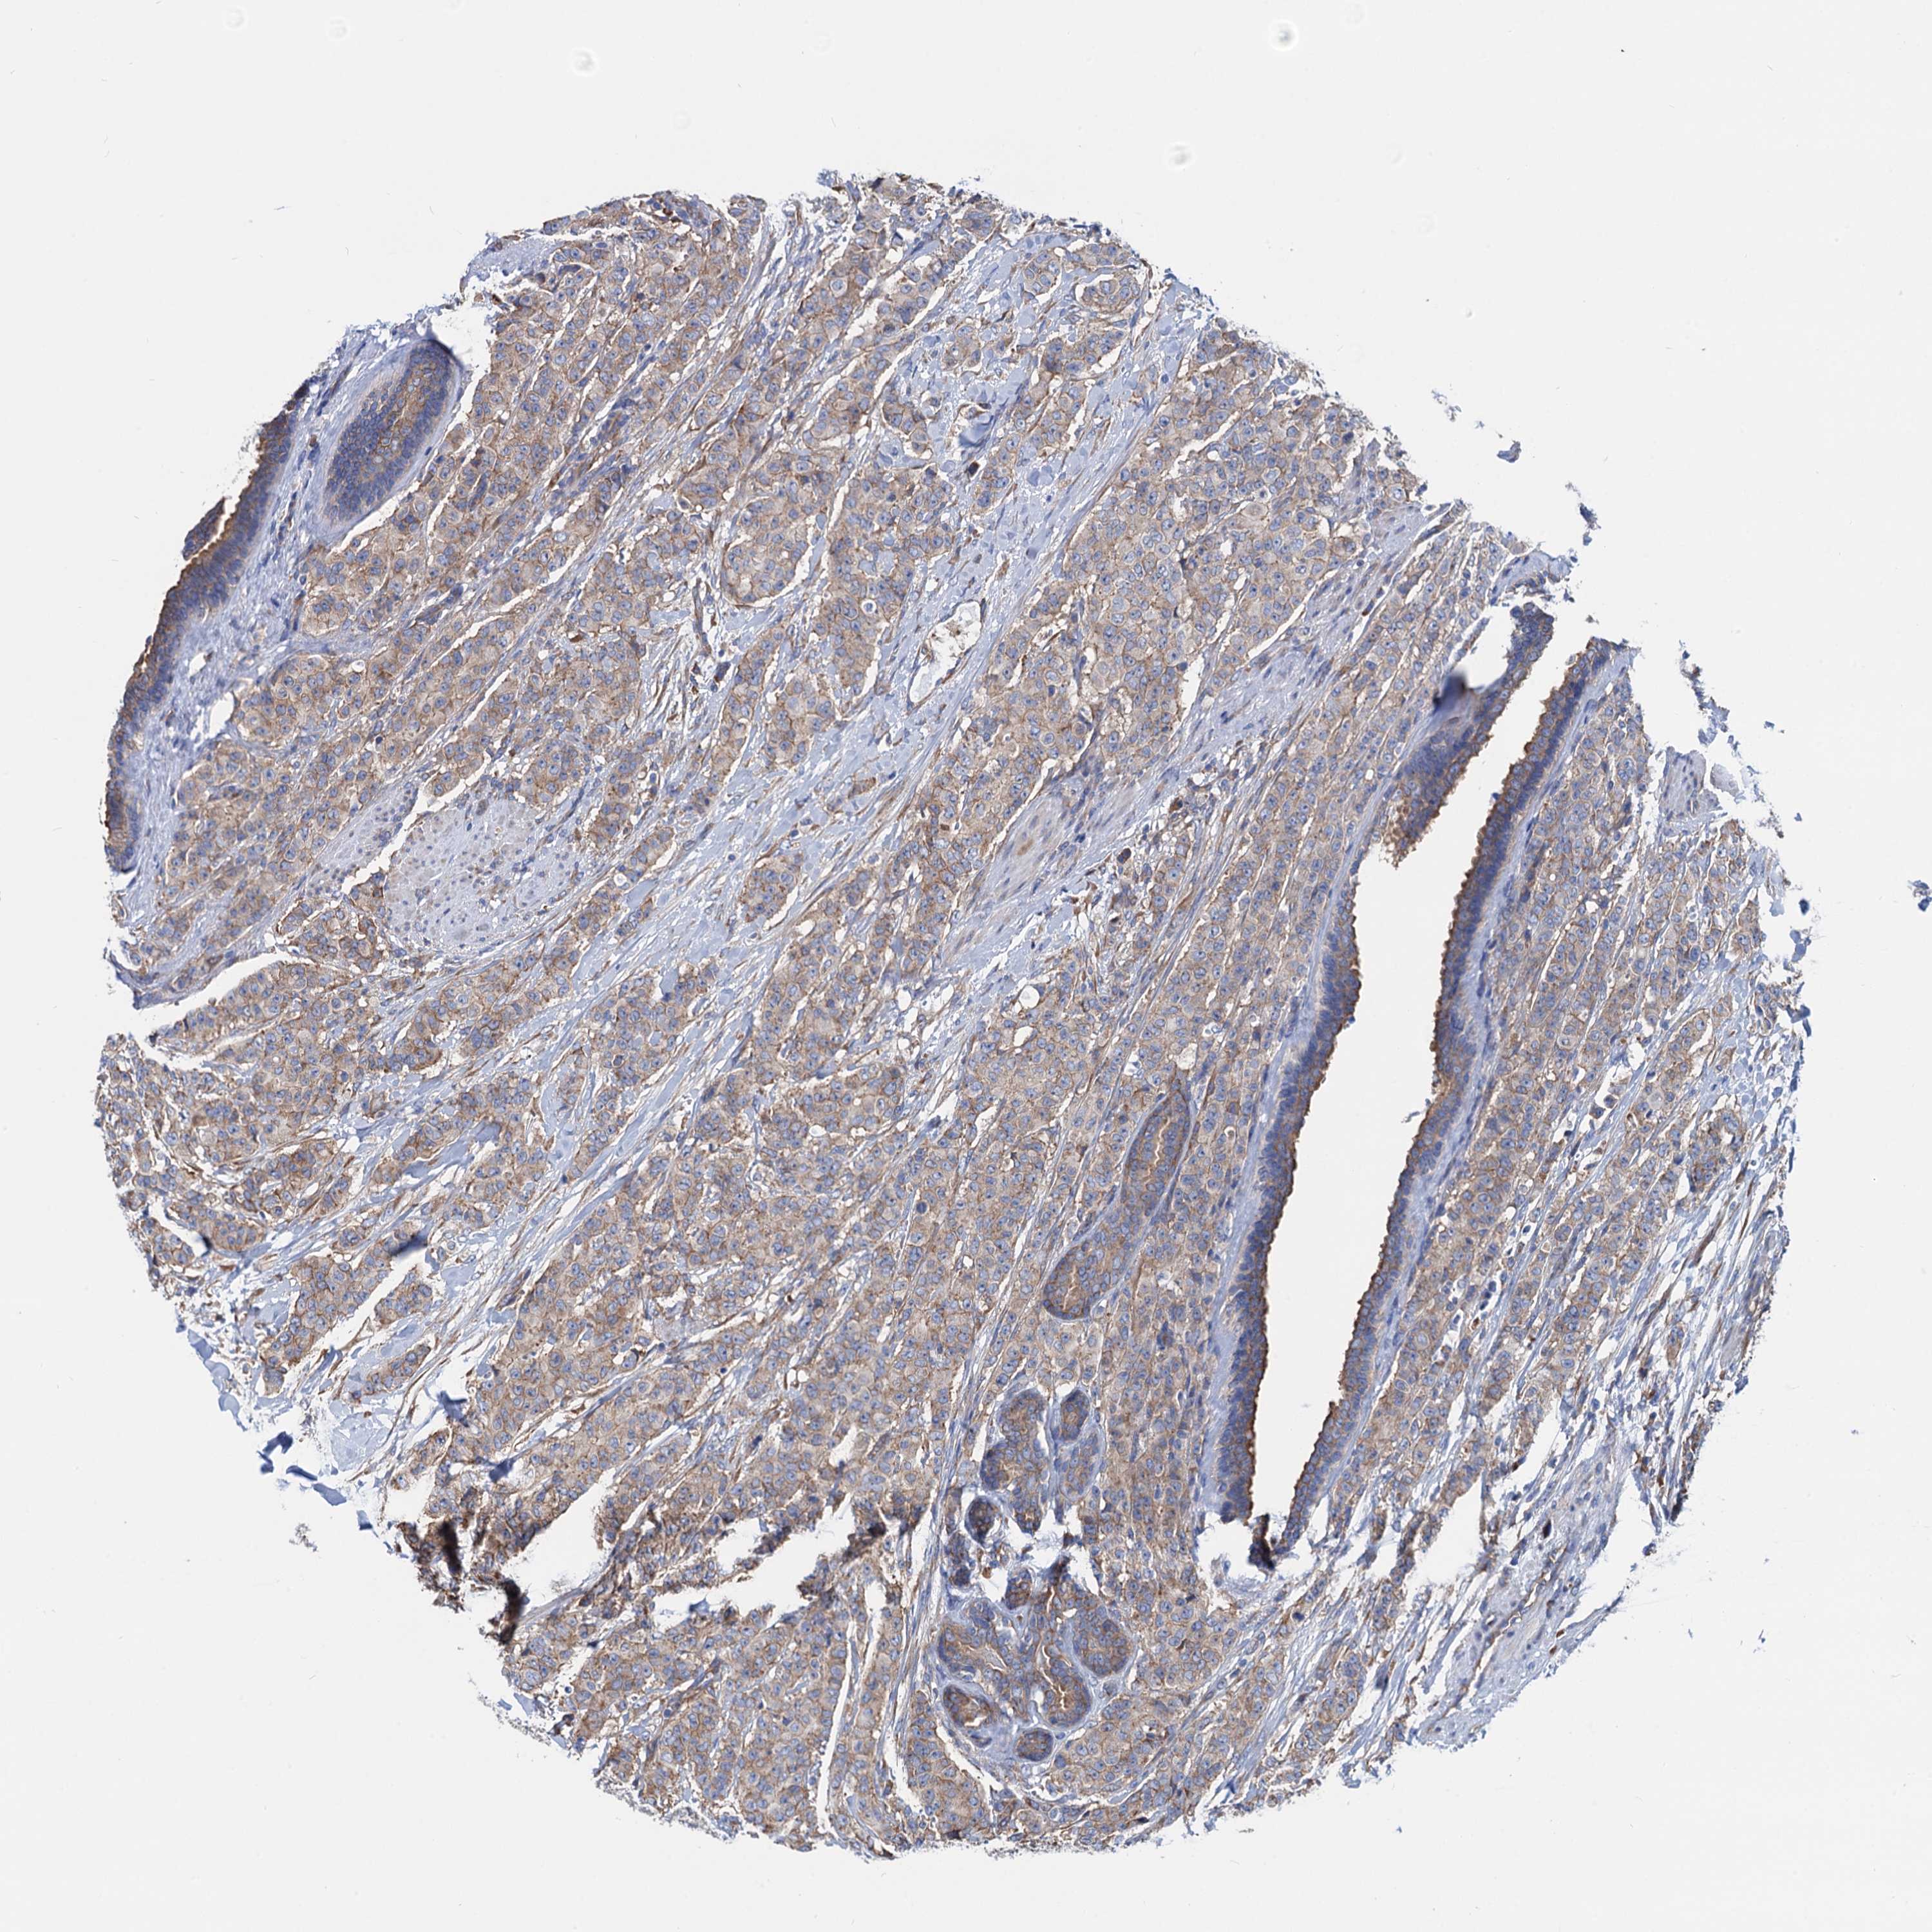

CANCER BREAST CANCER Show tissue menu

Breast cancer

Human cancer